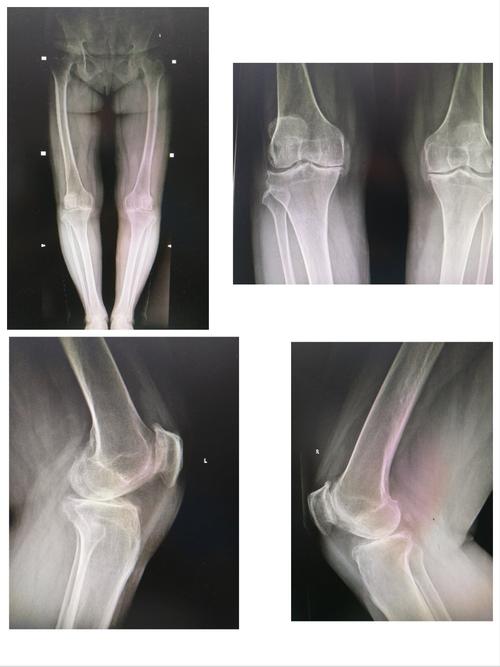

正常膝关节,正常膝关节正位片图片

但膝关节长期,用力,快速运动的情况就会磨损髌骨的软骨面,如自行车

有时候膝关节走路的时候不疼上下楼疼是什么原因呢

如图所示,正常膝关节的关节软骨光滑有弹性.

膝关节表面置换术x片示例

正常膝关节正位片图片

正常膝关节x线图片

正常膝关节x片

正常膝关节x光片